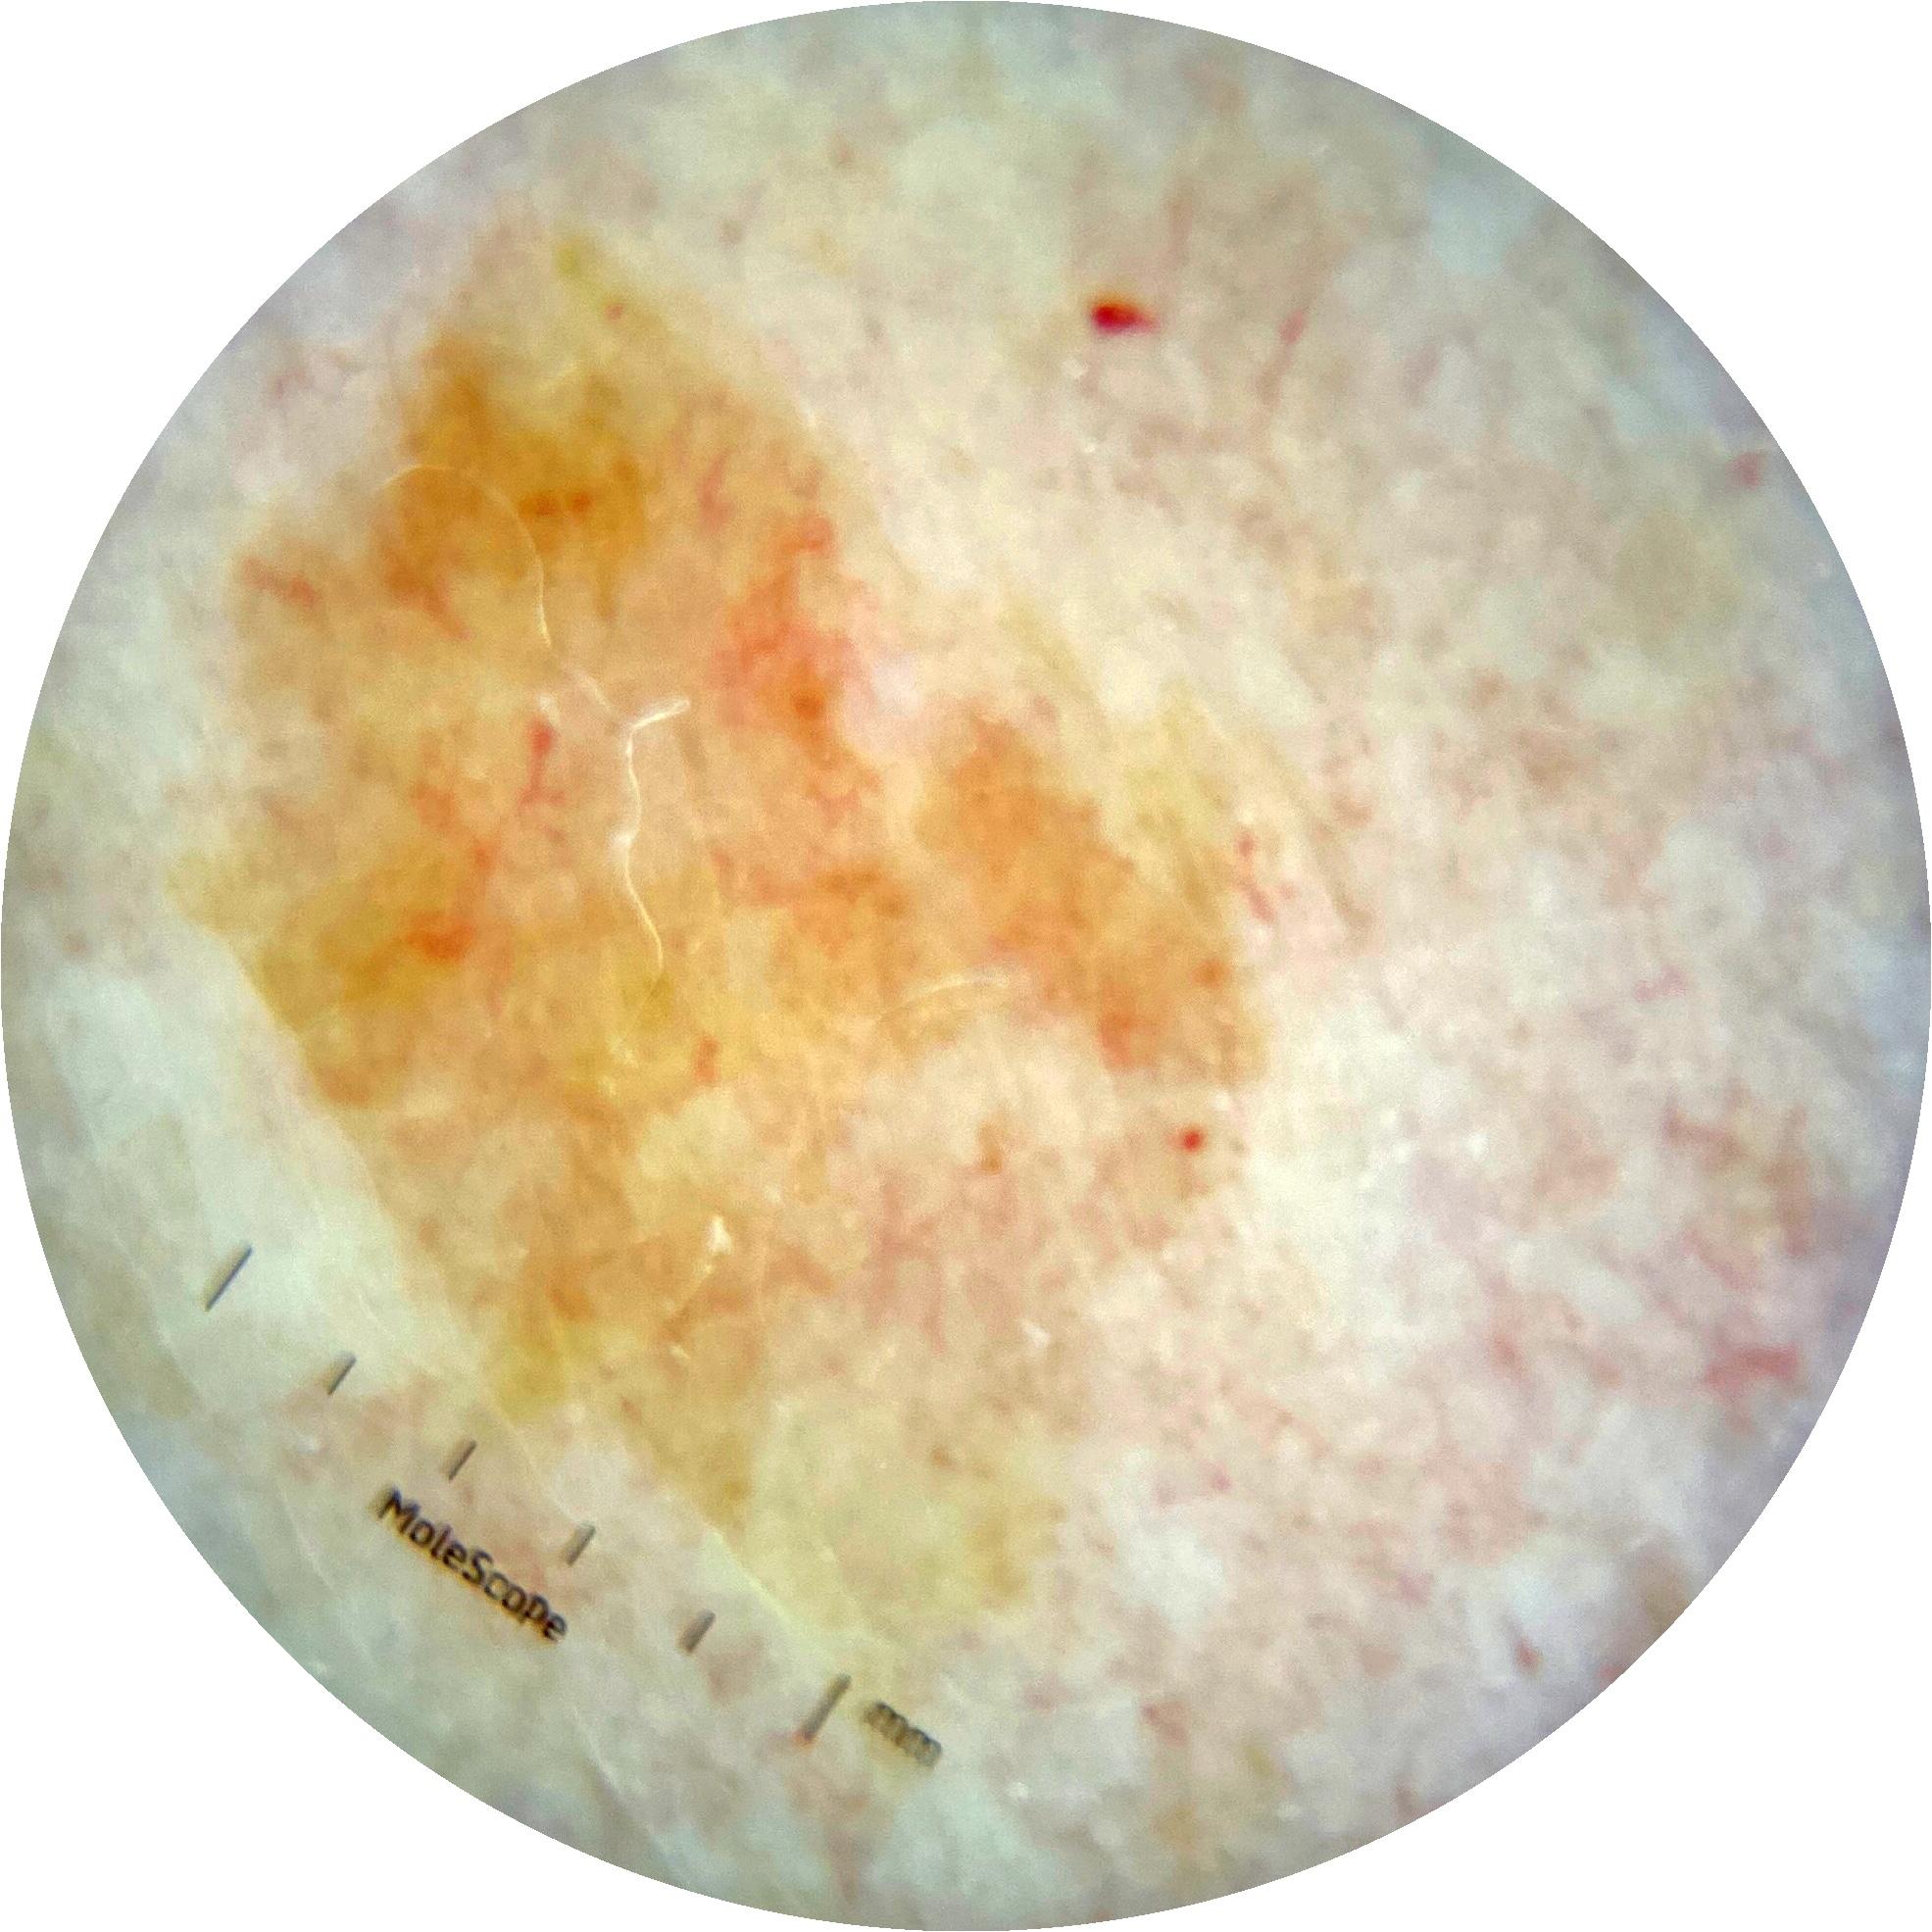

ISIC_7193897

MEL-SELF Trial, https://www.sydney.edu.au/medicine-health/our-research/research-centres/melself-project.html

IP_3751325

IL_3780211

Field Value

acquisition_day 251

age_approx 65

anatom_site_1 Lower extremity

anatom_site_general lower extremity

diagnosis_1 Benign

diagnosis_confirm_type single image expert consensus

image_type dermoscopic

lesion_id IL_3780211

patient_id IP_3751325

personal_hx_mm True

sex female